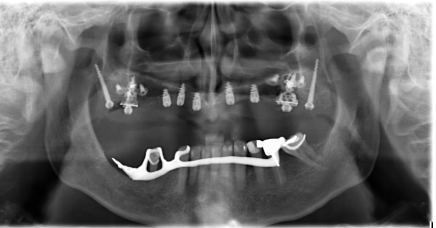

Figure 1 shows the panoramic radiograph of the patient at presentation. Radiographic examination using an orthopantomogram showed an edentulous upper jaw with moderate vertical bone resorption in the front and severe vertical resorption in the premolar and molar region.

Figure 1. panoramic radiograph of the patient at presentation

In the lower jaw, several teeth were present in the frontal region and in the right lateral region. Most of the teeth show a moderate to severe bone loss suggestive of chronic periodontitis.